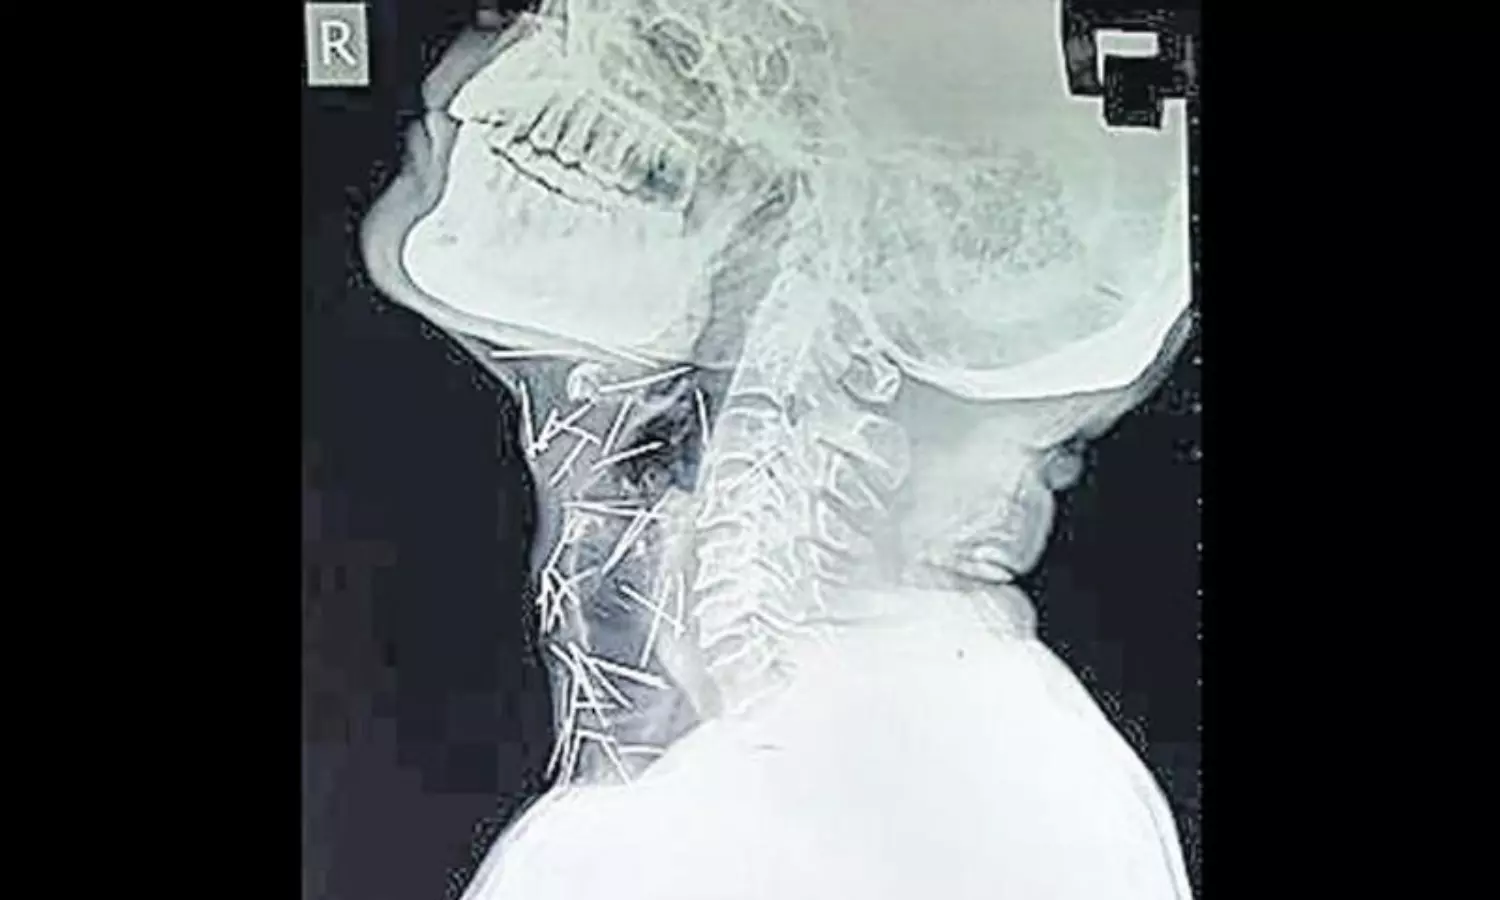

രാജസ്ഥാന്‍ സ്വദേശിയും 56 കാരനുമായ ബദ്രിലാല്‍ മീണ കാലുവേദനയും പ്രമേഹവും ശല്യപ്പെടുത്തിയപ്പോഴാണ് കഴിഞ്ഞ ഫെബ്രുവരിയില്‍ ആശുപത്രിയില്‍ പോകാന്‍ തീരുമാനിച്ചത്. കോട്ട റെയില്‍വെ സ്റ്റേഷന്‍ ആശുപത്രിയില്‍ വെച്ച് സര്‍ജറിയും നടന്നു. അതോടുകൂടി തന്റെ ബുദ്ധിമുട്ടുകളെല്ലാം അവസാനിച്ചുവെന്നായിരുന്നു മീണ കരുതിയത്. സര്‍ജറിയുടെ വിജയമറിയാനായി ഏപ്രില്‍ മാസമെടുത്ത എക്സറേയില്‍ തെളിഞ്ഞത് ചില നടുക്കുന്ന സത്യങ്ങളാണ്.. വിവിധ ഭാഗങ്ങളിലായി 75 മൊട്ടുസൂചികളാണ് ബദ്രിലാല്‍ മീണയുടെ ശരീരത്തിലുള്ളതായി എക്സറേയില്‍ കണ്ടെത്തിയത്.

റെയില്‍വെ ജീവനക്കാരനാണ് ബദ്രിലാല്‍ മീണ. ശരീരത്തില്‍ തൊലിക്കുള്ളിലായാണ് ഈ പിന്നുകള്‍ എല്ലാം എക്സറേയില്‍ കണ്ടത് എന്നതാണ് ഡോക്ടര്‍മാരെ അമ്പരപ്പിച്ചിരിക്കുന്നത്. കഴുത്തിലും, കൈകളിലും കാലിലുമായാണ് പിന്നുകളിലധികവും കണ്ടെത്തിയിട്ടുള്ളത്. ഇത്രയധികം മൊട്ടുസൂചികള്‍ എങ്ങനെ തന്റെ ശരീരത്തില്‍ വന്നുവെന്ന് ബദ്രിലാല്‍ മീണയ്ക്കും അറിയില്ല. ഇനി മറ്റാരെങ്കിലും ബദ്രിലാലിനെ ബോധം കെടുത്തിയോ മറ്റോ സൂചികളെ തൊലിപ്പുറത്തേക്ക് തുളച്ചു കയറ്റിയതാണെങ്കില്‍ അത്തരം അടയാളവും തൊലിപ്പുറമെ ഇല്ലതാനും. ഈ സമസ്യക്ക് ഉത്തരം തേടുകയാണ് ബദ്രിലാലിനെ ചികിത്സിക്കുന്ന ഡോക്ടര്‍മാരും.

ഇത്രയധികം മൊട്ടുസൂചികള്‍ ശരീരത്തിലുണ്ടെങ്കിലും അവയിലൊന്നുപോലും ആന്തരാവയവങ്ങളിലൊന്നും എത്തിയിട്ടില്ലായെന്നതും ഡോക്ടര്‍മാരെ കുഴക്കുന്നു. സൂചികള്‍ മീണ വിഴുങ്ങിയതായിരുന്നുവെങ്കില്‍ അവ എത്തേണ്ടിയിരുന്നത് വയറിനുള്ളിലോ അന്നനാളത്തിലോ ആയിരുന്നുവെന്ന് പറയുന്നു മീണയെ ചികിത്സിച്ച കോട്ട റെയില്‍വെ സ്റ്റേഷനിലെ സര്‍ജന്‍ ബി പാണ്ട.

പ്രമേഹബാധിതനായതിനാല്‍ സര്‍ജറി നടത്തി ഇത്രയധികം പിന്നുകളെ പുറത്തെടുക്കുക എന്നത് ബദ്രിലാലിന്റെ ജീവനെ അപകടത്തിലാക്കുമെന്ന് ഡോക്ടര്‍ ഭയക്കുന്നു. 40 സൂചികളാണ് തൊണ്ടയില്‍ കുടുങ്ങിക്കിടക്കുന്ന നിലയില്‍ കണ്ടെത്തിയിരിക്കുന്നത്. വലതു കാലില്‍ 25 എണ്ണവും രണ്ടെണ്ണം വീതം രണ്ട് കൈകളിലും തിരിച്ചറിഞ്ഞിട്ടുണ്ട്.